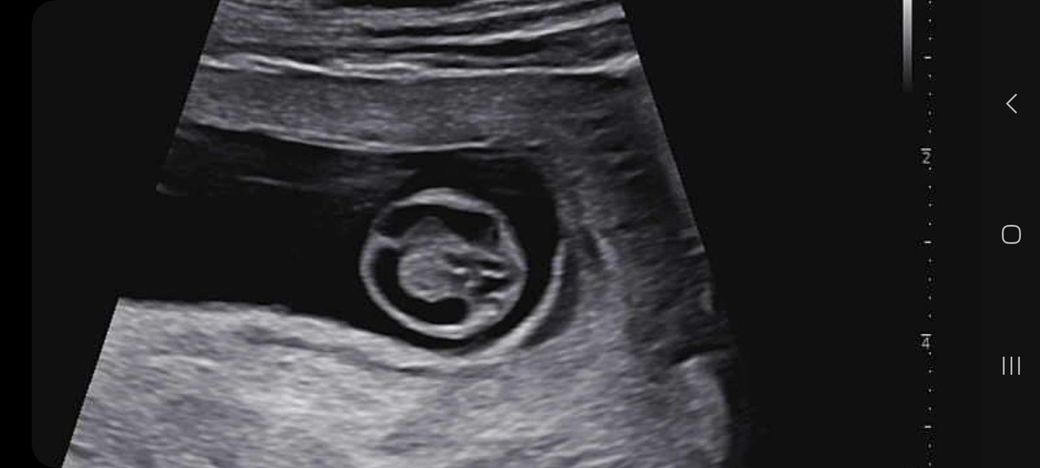

임신 10주차가 되었고 오늘 초음파 사진을 찍고왔어요

다 잘 크고있는데

머리 뇌 모양이 나비 모양이 아니라

2주뒤에 초음파 사진 볼 때 한번 더 보자 하더라구요

나비 모양이 되야 정상? 인데 아니라 신경이 쓰이네요

어떻게 보시는지 의견을 들려주심 감사합니다.

• 2번 째 사진